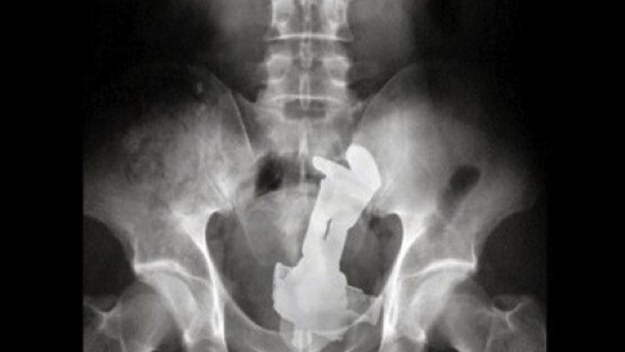

17. Ένα oμοίωμα ανδρικού μορίου